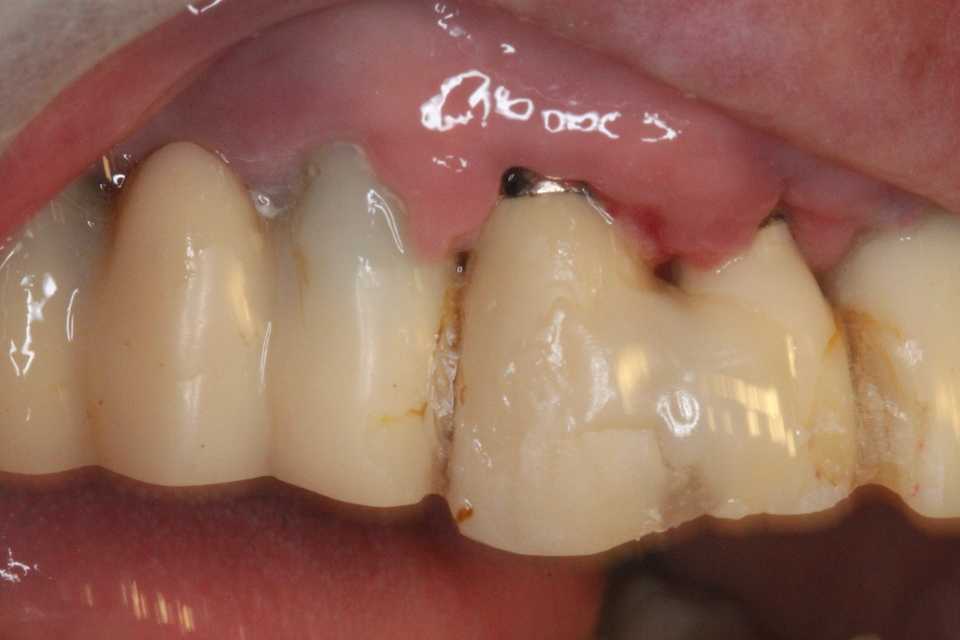

50代女性、左上5-7ブリッジ脱離、7番2次カリエス+Per(根尖性歯周炎)、強度の外傷性咬合この方、ひどい食いしばりで歯が壊れてしまう。噛み合わせの左下7番も歯冠が崩壊しつつある。7番はブリッジが脱離していて、内部は虫歯でドロドロ。Perつまり根管充填が緊密ではなく、歯根内部は細菌だらけで根の周りにはひどい炎症がある。まずはレントゲン写真から。7番の歯根の周りが炎症で黒くなっているのが分かると思う。ブリッジを全部外すと咬合が狂うので、とりあえず7番だけカットして内部を見てみた。根管充填材が見えるところまで軟化象牙質を除去して、3MIX+α-TCPを入れて根管内部を殺菌することにした。根管充填材の周りは黒くなっているのが見えると思うが、これは硫酸塩還元細菌の代謝産物の硫化鉄:FeSで、理想に反して根管充填材はゆるゆるの緊密充填ではないことを示している。このような状況は普通のことだ。歯根内部は細菌だらけということだが、ゆるゆるだから根管充填材を全部除去する必要もない。ゆるゆるの隙間から3MIX(抗菌剤)は浸透し根管は殺菌される。外傷力を弱めるために咬合調整を繰り返している。コア部分は隙間に細菌由来の黒色物質FeSがこびりつき、真っ黒。ポンティック下も細菌のコロニーでドロドロ歯質は残っているように見えるかもしれないが、ボンディング材が効く程度に軟化象牙質(虫歯)を除去すると、残根状態になる。つまり通常治療では抜歯しかないということだ。しかもPerでグラグラの動揺度2〜3、垂直性同様有りだ。とてもこのままではブリッジの支台には使えそうもない。ピンク色の根管充填材が見えると思うが、周りは真っ黒だ。その真っ黒になった隙間から細菌は侵入するし、3MIXも浸透する。こうではない緊密な根管充填治療は垂直加圧法でしか見られない。3MIX+α-TCPCR(ダイレクトボンディング)で覆う。これでないと微小漏洩が起こり失敗する。丸い形はラウンデッド・コアと呼び、この形が咬合力を内向きに集中させ歯根を守る。ポストは歯根の外側にこじるような応力を生じるので歯根を壊してしまいやすい。補綴物が必要な時はピンレッジで維持力を得る。これはCAD/CAMでは作れないだろう。これで2〜3週間様子をみる。外傷性咬合のコントロール(ナイトガードや行動療法)をしながら。つづく